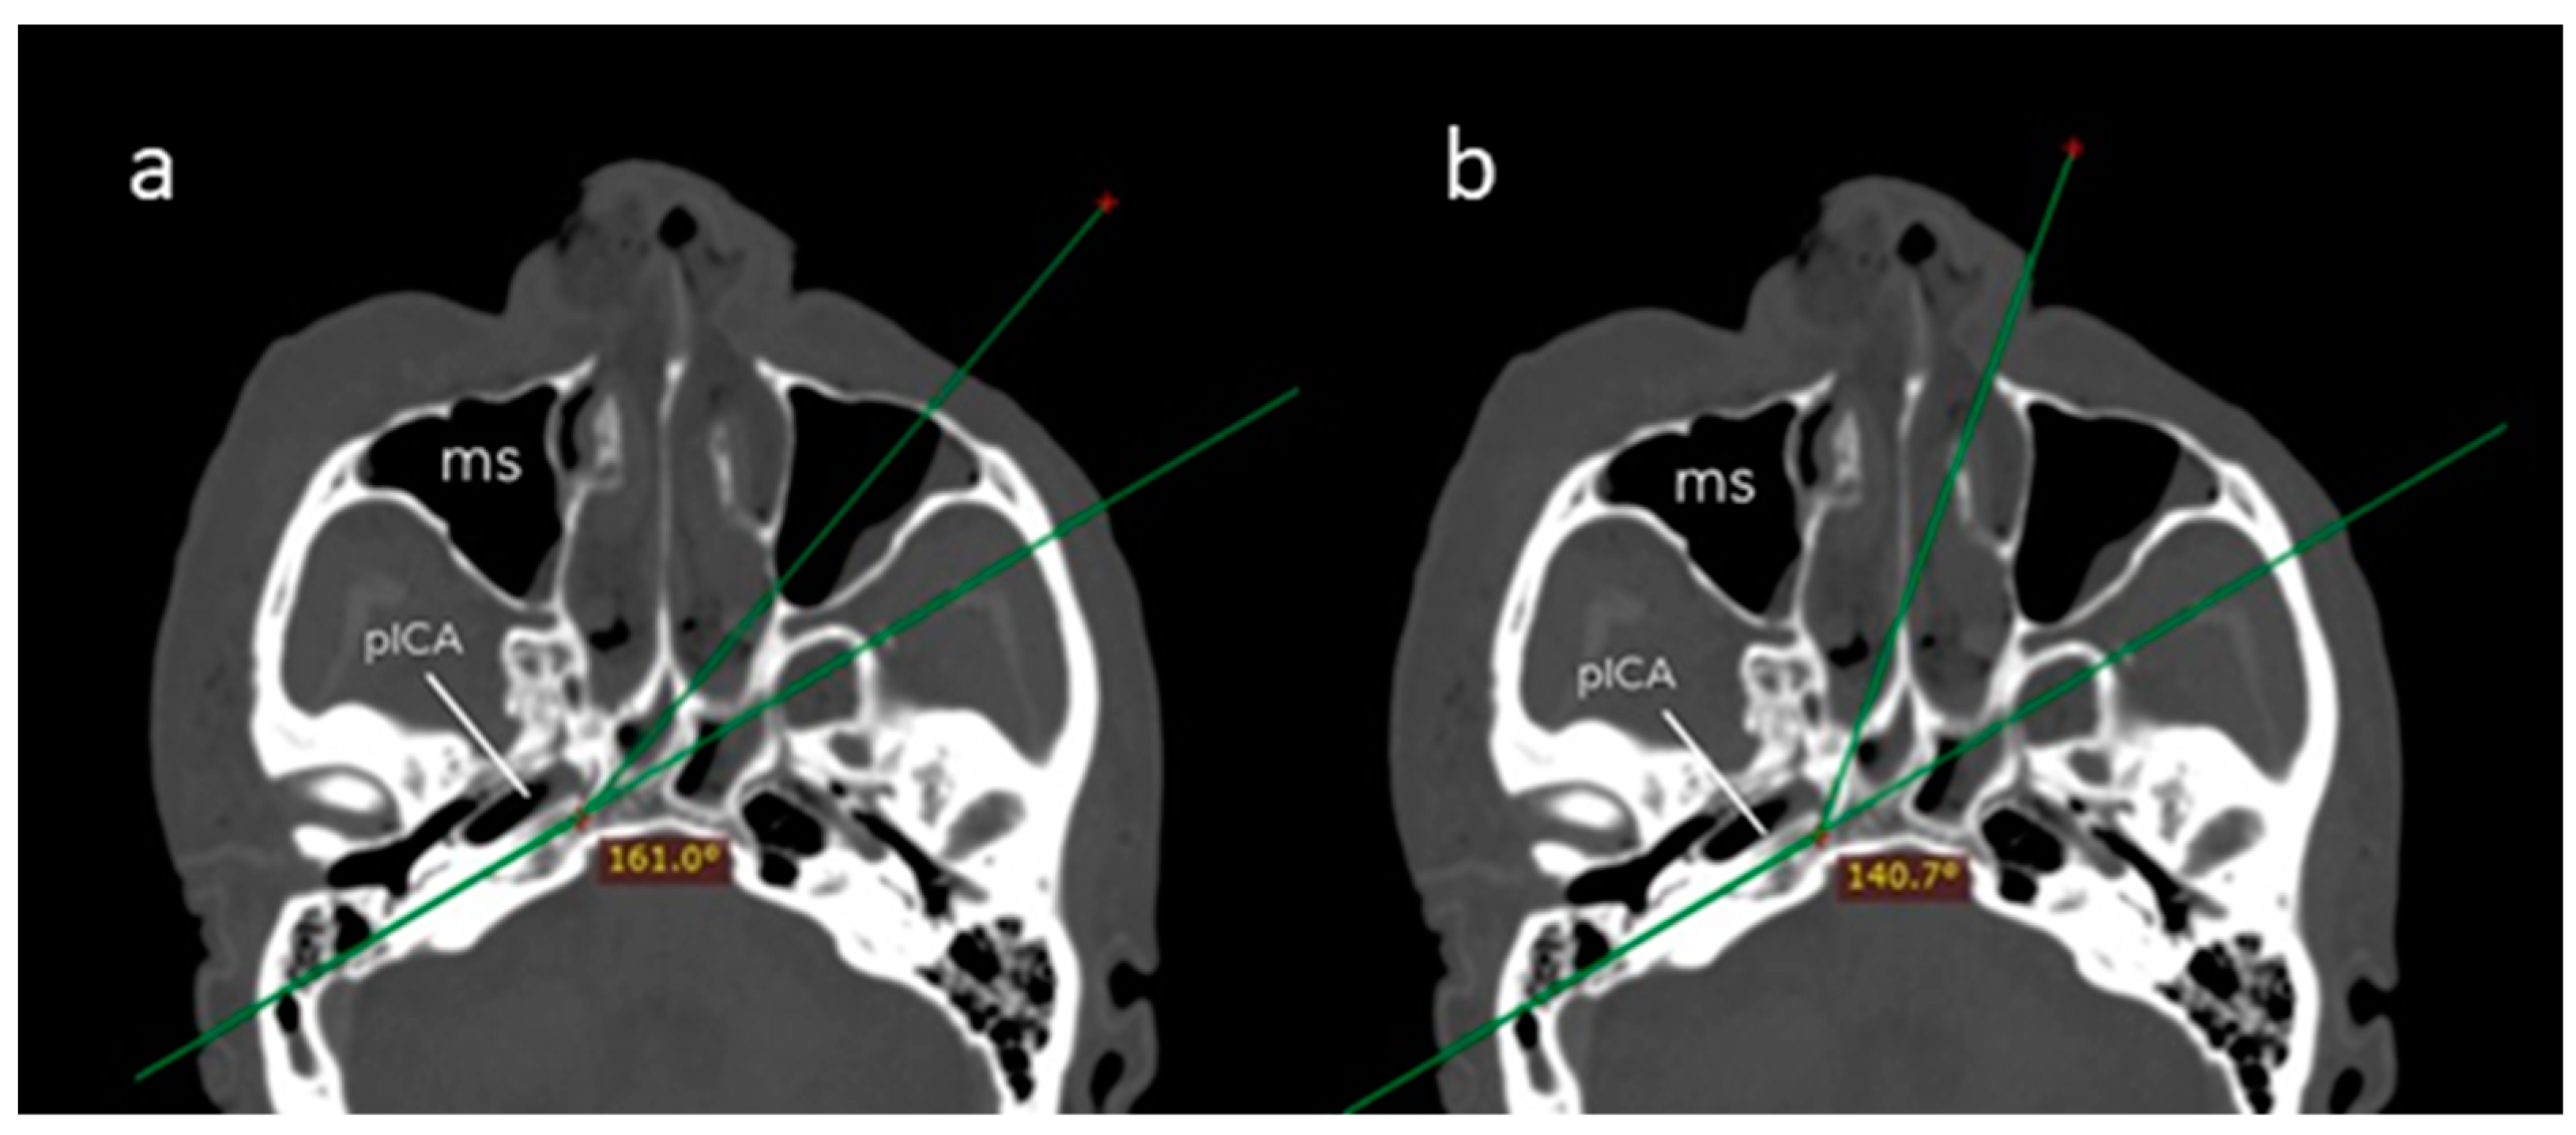

The angle of attack was significantly wider across the transmaxillary than the endonasal route (161.1° ± 8.6° vs. 140.6° ± 5.7°; p = 0.001). The mean gain of angle of attack through the transmaxillary corridor was 20.5° (±4.7°), affording a surgical trajectory more parallel to the major axis of the PA (Figure 5).

Figure 5.

Axial CT scan showing the angle of attack of the endoscopic endonasal (a) and contralateral transmaxillary (b) approaches. A line parallel to the axis of the petrous segment of the internal carotid artery is used as a reference to calculate the angles of attack. MS: maxillary sinus.

As detailed in Table 1, surgical filed depths were significantly shorter (74.3 ± 4.0 vs. 88.0 ± 5.8 mm; p = 0.001) and petrous drilling depths were significantly deeper (17.2 ± 4.0 vs. 11.0 ± 3.3 mm; p = 0.008) through the transmaxillary corridor.